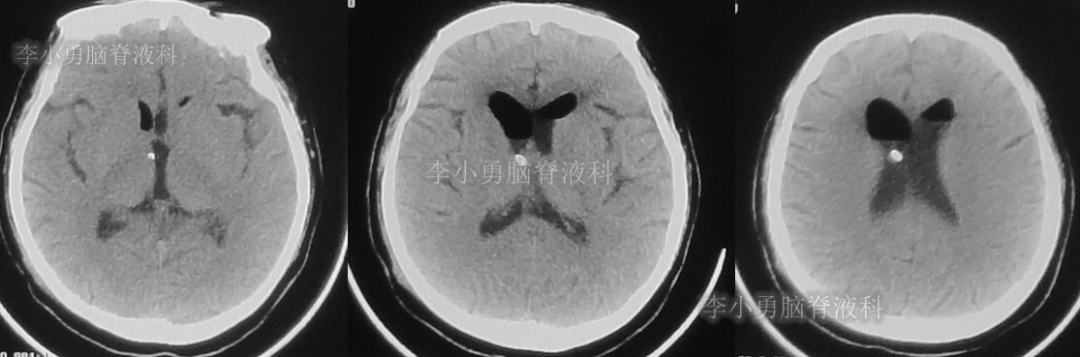

患者于2018年1月29日,突发头痛、头晕、恶心、呕吐,并高热40度。在当地医院门诊输入4天抗生素后发热缓解,但出现了双眼不能上视(眼球不能向上看)。5天后即2018年2月3日,在当地的第1家医院:浙江省海宁市某医院行头颅CT(图-1)发现脑室扩张,当地医院诊断为“梗阻性脑积水”。

图-1:2018年2月3日头颅CT